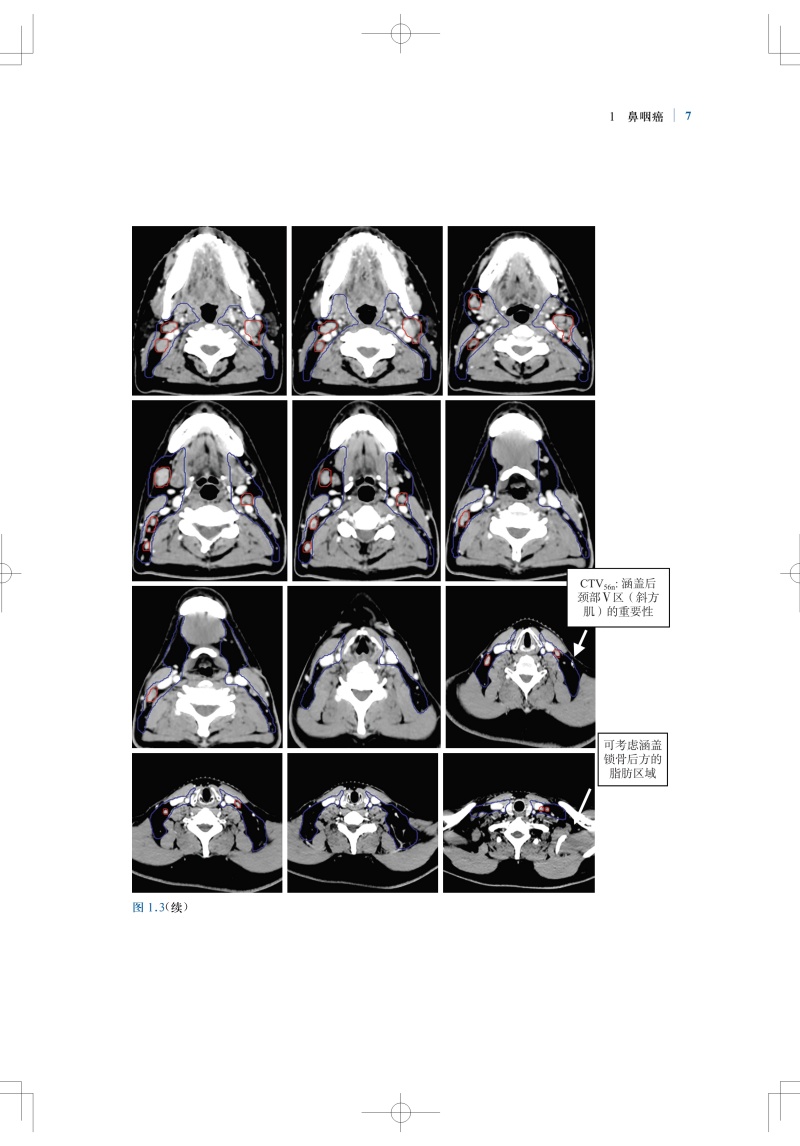

肿瘤放射治疗靶区勾画与射野设置是疗效的基石,精准的靶区范围的确定和勾画可确保肿瘤患者的放疗效果。全书结合大量影像图片,按章分别详细介绍了各种常见病变的具有临床依据的精确的CTV勾画和指南,包括鼻咽癌、甲状腺癌、早期乳腺癌、肺癌、直肠癌、前列腺腺癌、膀胱癌等;并对相关的淋巴引流区解剖进行了勾画,且逐层显示并说明注意事项。本书内容实用,可为放疗医师对常见肿瘤进行适形放疗和调强放疗时的靶区勾画及放射野设置提供指导和参考。